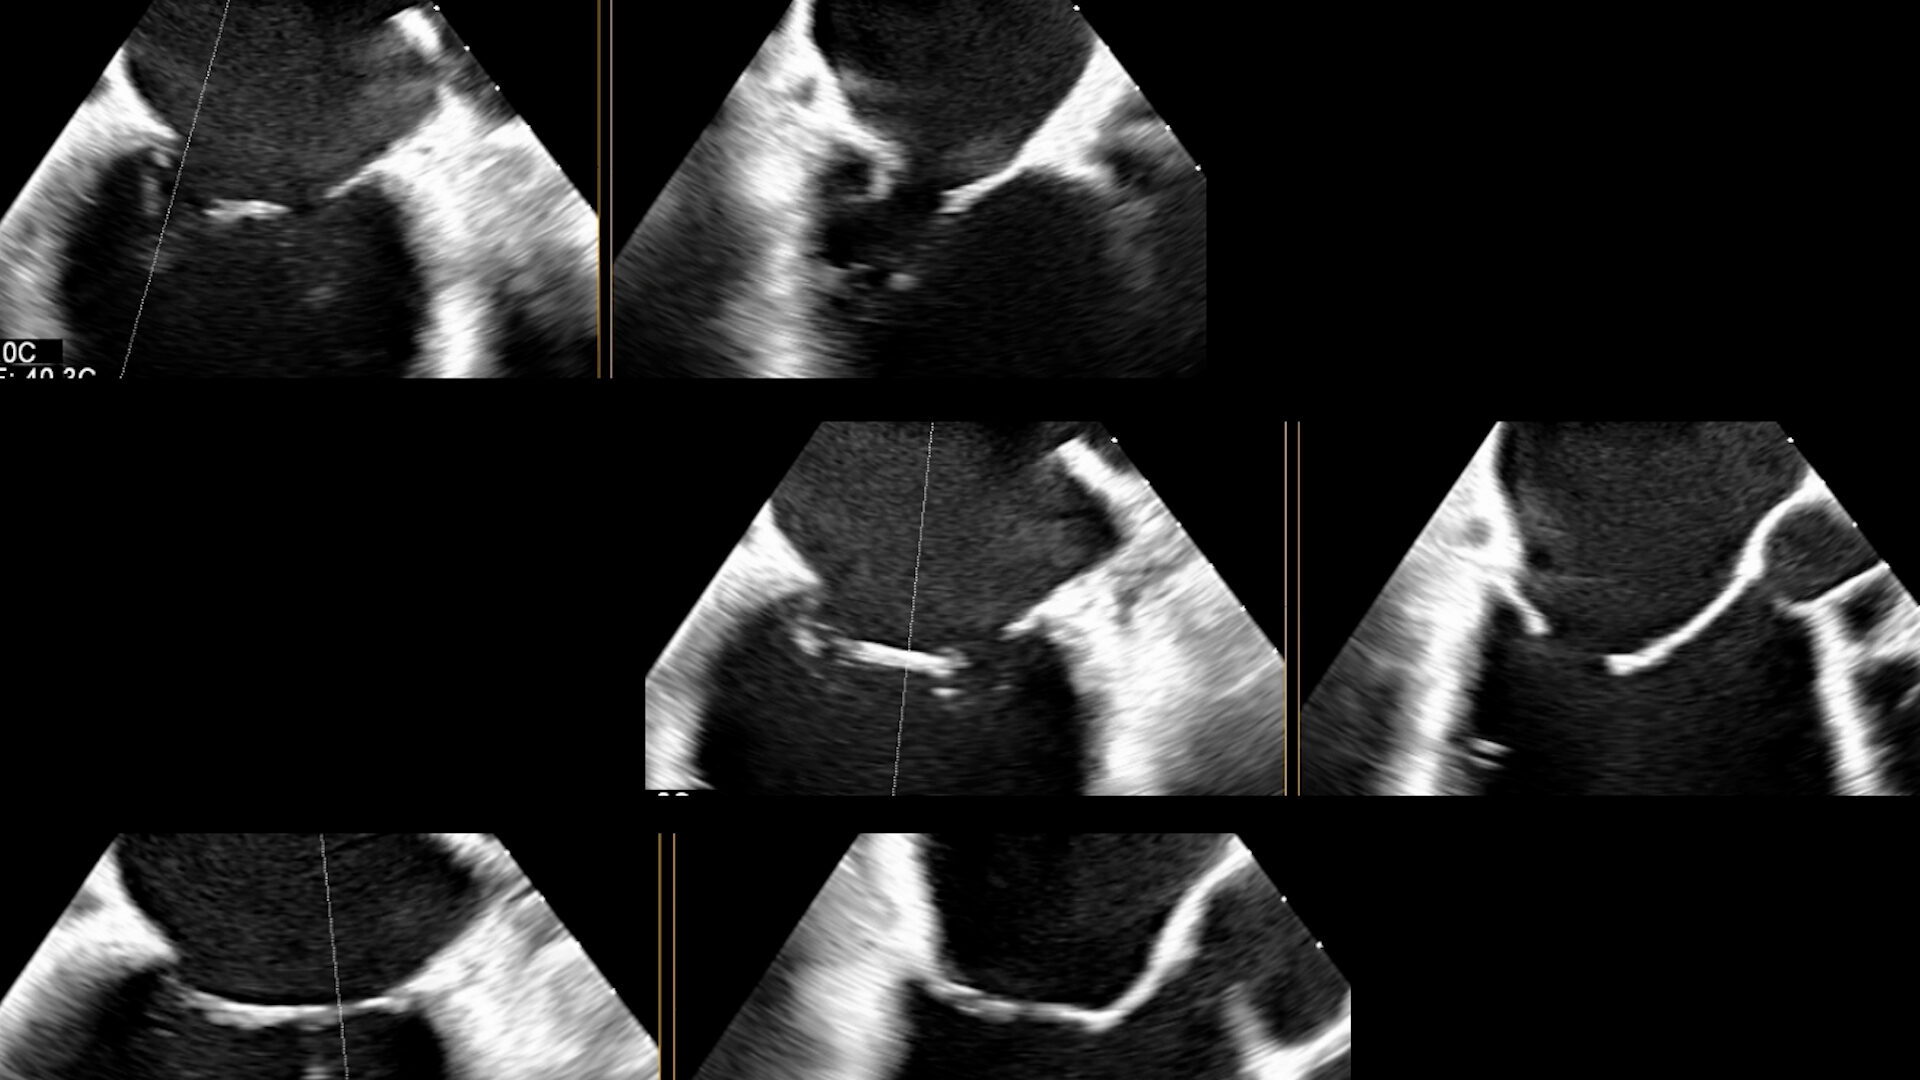

Il cardiologo Dott. Alessandro Vairo ci spiega quali sono le applicazioni pratiche dell'ecografia 3D per lo studio della valvola tricuspide

Il cardiologo Dott. Alessandro Vairo ci spiega quali sono le applicazioni pratiche dell'ecografia 3D per lo studio della valvola mitrale

Il cardiologo Dott. Alessandro Vairo ci spiega quali sono le applicazioni pratiche dell'ecografia 3D per lo studio delle valvole cardiache e l'assistenza agli interventi a